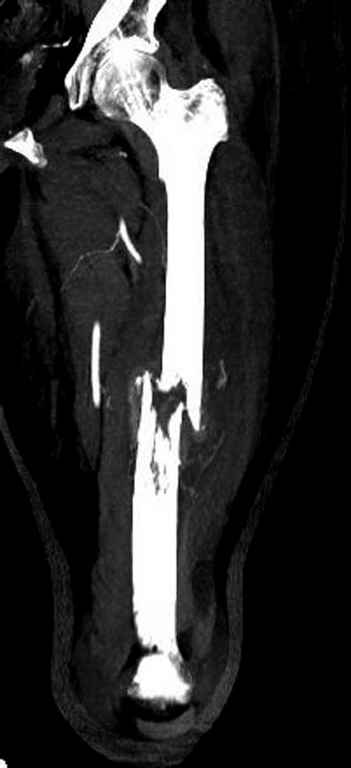

Здесь случай 66 летней пациентки со спонтанными болями в левой нижней

конечности, обратилась в приемное, сделаны снимки бедра и КТ.

Патологический перелом бедра, конечность на вытяжении.

Имя     : Pathologic Femur injury AP.jpg